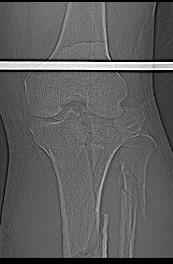

АЛ> Интересует срок проведения оперативного вмешательства,

Интрамедуллярный остеосинтез диафизарного перелома тут возможен, но в первую очередь надо с помощью КТ уточнить повреждение суставного конца. Импрессионный перелом наружного мыщелка явный есть, может, и медиальная колонна повреждена, так что надо в первую очередь планировать открытую репозицию с замещением дефекта с фиксацией пластиной или аппаратом. Если получается технически, можно поверх уже синтезированного стержнем диафиза.

Уважаемый Александр Николаевич! Прошу прощения за некачественные сканы. КТ вообще-то реально, но сложности с транспортировкой больного в соседний корпус (такая перевозка и перекладывание для больных - дополнительная травма). По Р-граммам медиальный отдел вроде целый, но наружный мыщелок "отклячен" и суставная поверхность явно просела. У нас весь вопрос в методе фиксации или же их сочетании - одна пластина, опорная пластина и стержень (я так понял, что вы предлагаете сначала фиксировать диафиз, а потом заняться мыщелком?), винты и стержень, аппарат...Опять же состояние м/тканей (плотный отек, кровоизлияние)...

При наличии перелома тибиал плато не слишком ли расширяете показания блокирующего интрамедулярного остеосинтеза? И трудно поверить что невозможно транспортировать больного в соседний корпус для исследования. А тогда как c больными с политравмой или множественными сочетанними повреждениями?

Теоретически наверное можно фиксировать интрамедуллярным гвоздем, но при наличии набора пластин, какой смысль? Тем более при наличии внутрисуставного перелома интрамедулярный остеосинтез не создасть преимущества ранней нагрузки.

"Плотный отек и кровеизлияние" результат осевших мыщелков и уменьшения высоты конечности. Кондиции мягкой ткани в данном этапе не позволяет без риска делать операцию. Если у больного отсутствует вытяжение, тогда для улучшения состоянии мягкой ткани и для дистракции надо установить любой мостовидный наружный фиксатор от бедра к голени. Больной получит свободу, будеть передвигаться с помощью костылей и тогда сделайте нужные исследования включая Компьютерную Томограмму.

После утихания отеков и образования "wrinkle sign" сделать операцию на тибиал плато. Вариант длинная пластина с латеральной стороны. Надо приподнять импрессию с ауто или синтетическим графтом. Учитывая перелом медиального мыщелка antiglade пластина из минидоступа медиально..

В своем арсенале все компании имеют длинные перкутанные пластины. Преимущества примерное как от гвоздя, открывается только латеральная стороны на уровне перелома тибиал плато, а в остальном перкутанный Jig Insertion Device.